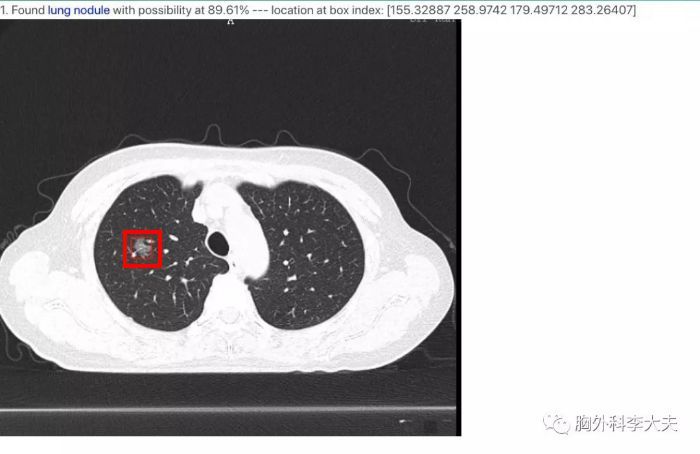

经过定焦大叔跟李医生确认,肺结节一般指的是3CM以下的肺部阴影,但是临床上呢,大于1CM的结节,医生很容易判断出它的性质,只有1CM以下,大多数几毫米的结节,容易在临床上存在争议,李医生同学的结节就是这种“微结节”,只有5MM)

随着胸部CT检查的普及,我们发现肺结节的机会越来越多。发现了肺结节,首先不要惊慌,因为研究证实很多人肺里面都有肺结节,有的研究甚至能达到40%-50%。

事实上CT发现的肺结节大约有90%是良性的。因为我们在几十年的生活中,肺里面难免会吸入一些灰尘、细菌,会有一些炎症,炎症吸收以后就可能遗留一些类似于皮肤瘢痕的肺纤维条索,肺结节等等。

但也不要忽视它的存在,因为早期的肺癌确实通常表现为小的肺结节。